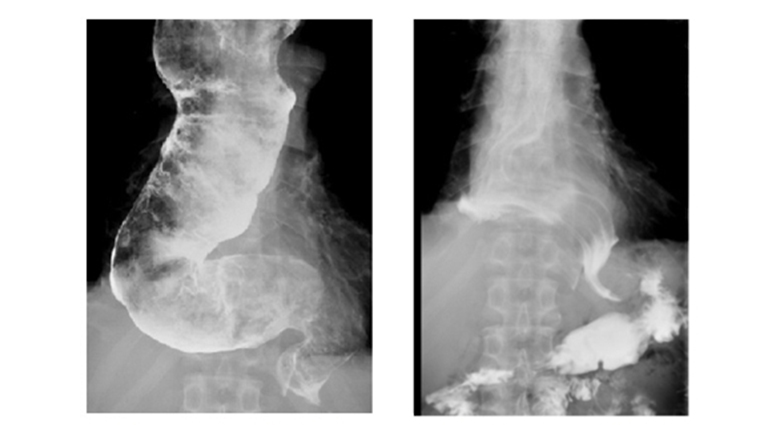

經上消化道內視鏡檢查發現,食道大幅彎曲擴張,且充滿未消化的食物。以食道鋇劑攝影觀察食道呈S型彎曲與鳥嘴型表現,吞入的顯影劑停留在食道無法進入胃部。進一步接受新一代高解析度食道動力學檢查,發現食道收縮蠕動功能喪失合併下食道括約肌壓力增加,確診為食道遲緩不能症第1型,在接受經口內視鏡下食道括約肌切開術(POEM)後,第2天即恢復進食且無吞嚥困難症狀,1個月後體重恢復,順利解決了10多年來的困擾。

▲手術前食道攝影圖(左)、手術後食道攝影圖(右)。(圖/臺北榮民總醫院提供)